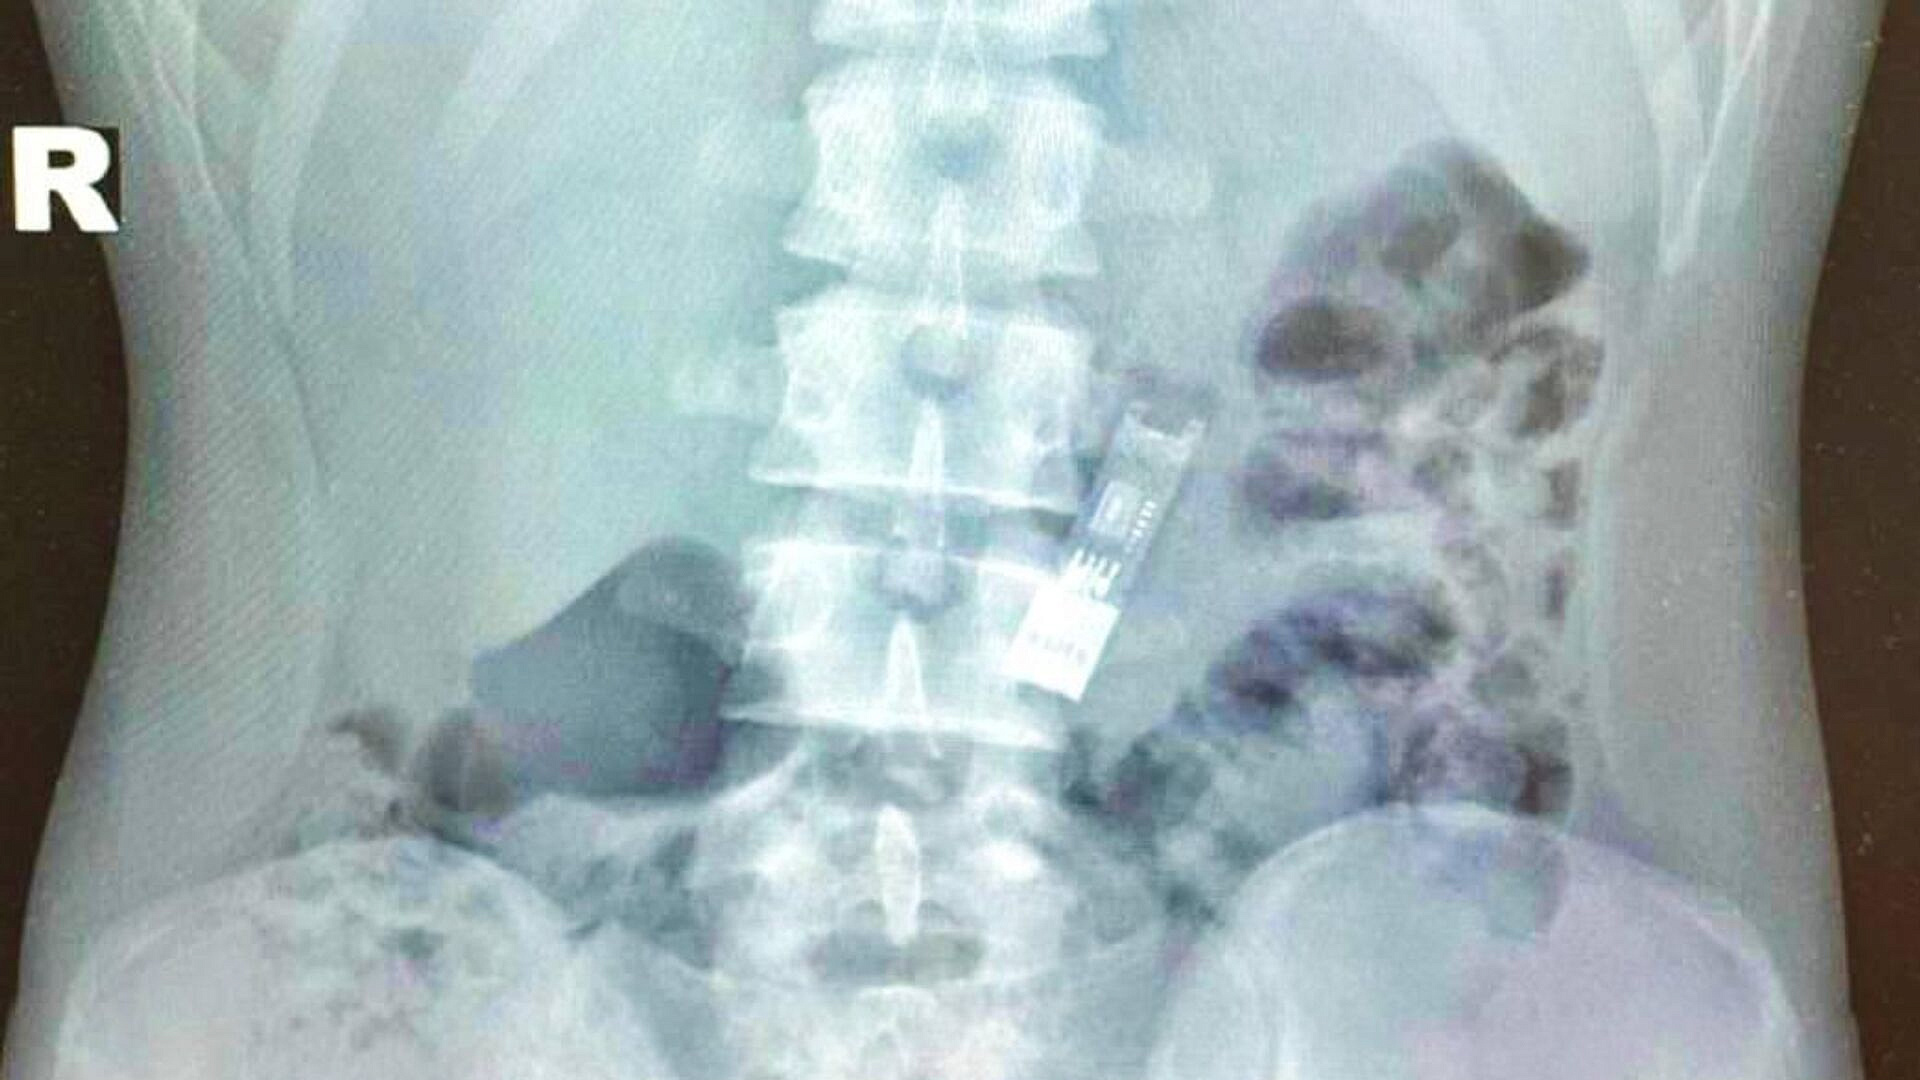

Врачи Детского клинического центра имени Л.М. Рошаля извлекли из желудка школьника флешку с его домашним заданием по информатике. 16-летний мальчик уже выписан из больницы, а его работа была успешно принята в школе, сообщили в министерстве здравоохранения Московской области.

"Непредвиденный инцидент с домашним заданием произошел с 16-летним подростком, который обратился в Детский клинический центр имени Л. М. Рошаля. Он выполнил задание и загрузил его на флешку, после чего, играя, начал вертеть флешку перед лицом. В какой-то момент он случайно проглотил её. Иногда инородные тела выходят естественным образом, на что мальчик надеялся, но в этом случае этого не произошло, и его семья обратилась за медицинской помощью", - отметили в пресс-службе.

На следующий день мальчика выписали домой. Флешка не успела причинить вред организму и осталась работоспособной. Его домашняя работа была успешно принята в школе.